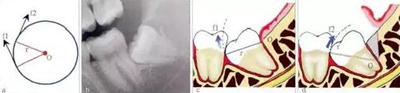

3.3.1 轉(zhuǎn)動軸心與圓弧運(yùn)動

這一原理在前傾或水平阻生智齒的拔除中運(yùn)用最廣。可以通過改變牙體轉(zhuǎn)動脫位時的運(yùn)動軸心,來改變牙體上各點(diǎn)的運(yùn)動方向(圖4),從而避開阻力而使牙齒脫位。但在此過程中,牙槽窩的擠壓變形仍不可避免。尤其是舌側(cè)骨板的骨折,更是經(jīng)常發(fā)

生的事件。要進(jìn)一步減少對牙槽窩的擠壓,則需要對牙根進(jìn)行進(jìn)一步的切割。

4.jpg

圖4 轉(zhuǎn)動軸心與圓弧運(yùn)動。在圓周運(yùn)動(旋轉(zhuǎn))中,圓周上所有點(diǎn)的運(yùn)動方向(f1、f2)均為切線方向,與通過該點(diǎn)的半徑(r)相垂直(圖a)。當(dāng)牙齒發(fā)生旋轉(zhuǎn)脫位時,其阻力點(diǎn)的運(yùn)動方向會隨著轉(zhuǎn)動的軸心點(diǎn)的變化而變化,從而避開阻力。前傾

阻生智齒(圖b)脫位時,阻力分析如圖c所示,因阻力點(diǎn)位于旋轉(zhuǎn)中心(O)的下方,旋轉(zhuǎn)脫位時,其阻力點(diǎn)的運(yùn)動方向(f1)是向前上的,被鄰牙所阻擋。如果按照圖d所示,去除遠(yuǎn)中骨質(zhì)(灰色部分)或切割牙體(r)后,旋轉(zhuǎn)中心(O)下移,阻

力點(diǎn)的運(yùn)動方向就改變?yōu)橄蚝笊希╢2),而得以避開鄰牙阻擋而脫位。